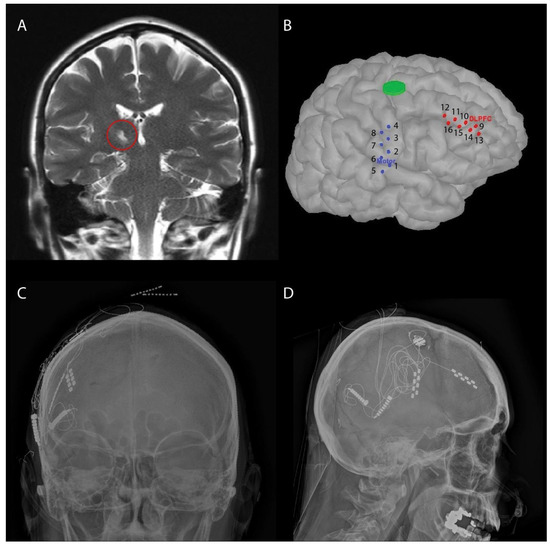

Personalizing Dual-Target Cortical Stimulation with Bayesian Parameter Optimization Successfully Treats Central Post-Stroke Pain: A Case Report

by Evan M. Dastin-van Rijn, Seth D. König, Danielle Carlson, Vasudha Goel, Andrew Grande, Donald R. Nixdorf, Sarah Benish, Alik S. Widge, Ziad Nahas, Michael C. Park, Tay I. Netoff, Alexander B. Herman and David P. Darrow

Brain Sci. 2022, 12(1), 25; https://doi.org/10.3390/brainsci12010025 - 26 Dec 2021

Central pain disorders, such as central post-stroke pain, remain clinically challenging to treat, despite many decades of pharmacological advances and the evolution of neuromodulation. For treatment refractory cases, previous studies have highlighted some benefits of cortical stimulation. Recent advances in new targets for [...] Read more.

Central pain disorders, such as central post-stroke pain, remain clinically challenging to treat, despite many decades of pharmacological advances and the evolution of neuromodulation. For treatment refractory cases, previous studies have highlighted some benefits of cortical stimulation. Recent advances in new targets for pain and the optimization of neuromodulation encouraged our group to develop a dual cortical target approach paired with Bayesian optimization to provide a personalized treatment. Here, we present a case report of a woman who developed left-sided facial pain after multiple thalamic strokes. All previous pharmacologic and interventional treatments failed to mitigate the pain, leaving her incapacitated due to pain and medication side effects. She subsequently underwent a single burr hole for placement of motor cortex (M1) and dorsolateral prefrontal cortex (dlPFC) paddles for stimulation with externalization. By using Bayesian optimization to find optimal stimulation parameters and stimulation sites, we were able to reduce pain from an 8.5/10 to a 0/10 during a 5-day inpatient stay, with pain staying at or below a 2/10 one-month post-procedure. We found optimal treatment to be simultaneous stimulation of M1 and dlPFC without any evidence of seizure induction. In addition, we found no worsening in cognitive performance during a working memory task with dlPFC stimulation. This personalized approach using Bayesian optimization may provide a new foundation for treating central pain and other functional disorders through systematic evaluation of stimulation parameters. Full article